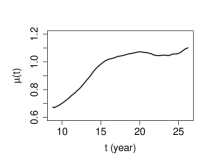

The estimated variance of the measurement error is by the method proposed in Section 3, by PACE and by LM, respectively. The estimates of the covariance surface are depicted in Figure 3. We observe that, the estimates produced by SNPTM and SNPTF are similar in the diagonal region, while visibly differ in the off-diagonal region. For this dataset, the upward off-diagonal parts of the estimated covariance surface by SNPTF seem artificial, so we recommend the SNPTM estimate for this data. For the PACE estimate, due to the missing data in the off-diagonal region and insufficient observations at two ends of the diagonal region, it suffers from significant boundary effect.

The mean function estimated by SNPTM111SNPTM, SNPTF and PACE use the same method to estimate the mean function. shown in the left panel of Figure 4 and found similar to its counterpart in Lin et al. (2019), suggests that the spinal bone mineral density increases rapidly from age 9 to age 16, and then slows down afterward. The mineral density has the largest variation around age 14, indicated by the variance function estimated by SNPTM222SNPTM and SNPTF use the same method to estimate the variance function. and shown in the middle panel of Figure 4. As a comparison, the PACE estimate, shown in the right panel of Figure 4, suffers from the boundary effect that is passed from the PACE estimate of the covariance function, because the PACE method estimates the variance function by the diagonal of the estimated covariance function.